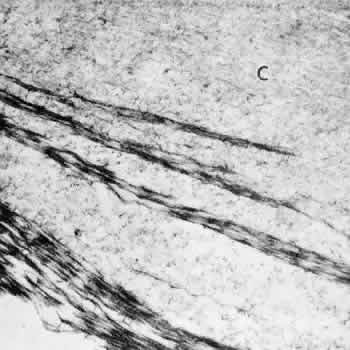

By light microscopy, zonular fiber bundles are eosinophilic, PAS-positive structures, often appearing to be ribbons connected by a paler interbundle “membrane” (Fig. 6). By scanning electron microscopy, the ribbons appear as groups of striated fiber bundles held together by a loose fibrogranular meshwork. Each fiber is composed of fibrils 10 nm in diameter, highly oriented and closely aggregated. Ultrastructurally, these fibrils have a tubular profile in cross section and a microperiodicity of 12 to14 nm seen along the fibril (Fig. 7). Dyes that precipitate and bind to polysaccharides show irregular granules and rod-like associated material on and between the fibrils.

Fig. 7. Zonular fibrils average 10 nm in diameter. Most show a microperi-odicity of 12 nm (arrow) and they frequently appear hollow in cross section (small arrows). (TEM, × 81,600) Inset. C is lens capsule. The dark dots and filaments adherent to each zonular fibril are polysaccharide components preserved by fixatives containing Alcian blue (TEM, × 100,000).